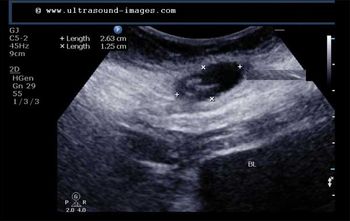

This 53 year-old woman has a uterine lesion and irregular bleeding. Which of the following is the correct diagnosis?